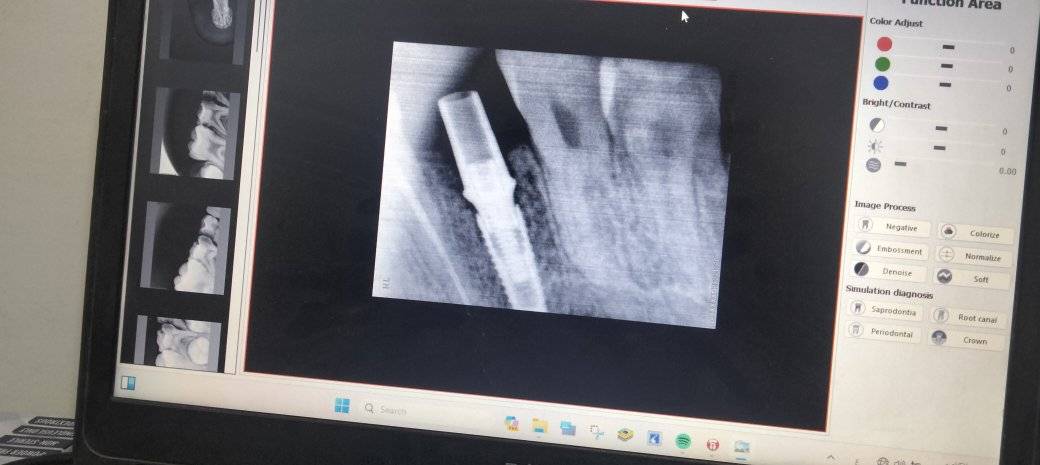

د. محمد حماد - زراعة TB Implant System في الفك العلوي

د. محمد حماد - تم التخطيط لزراعة فورية باستخدام TB Implant System في الفك السفلي الأيسر لتعويض فقد ضرس.